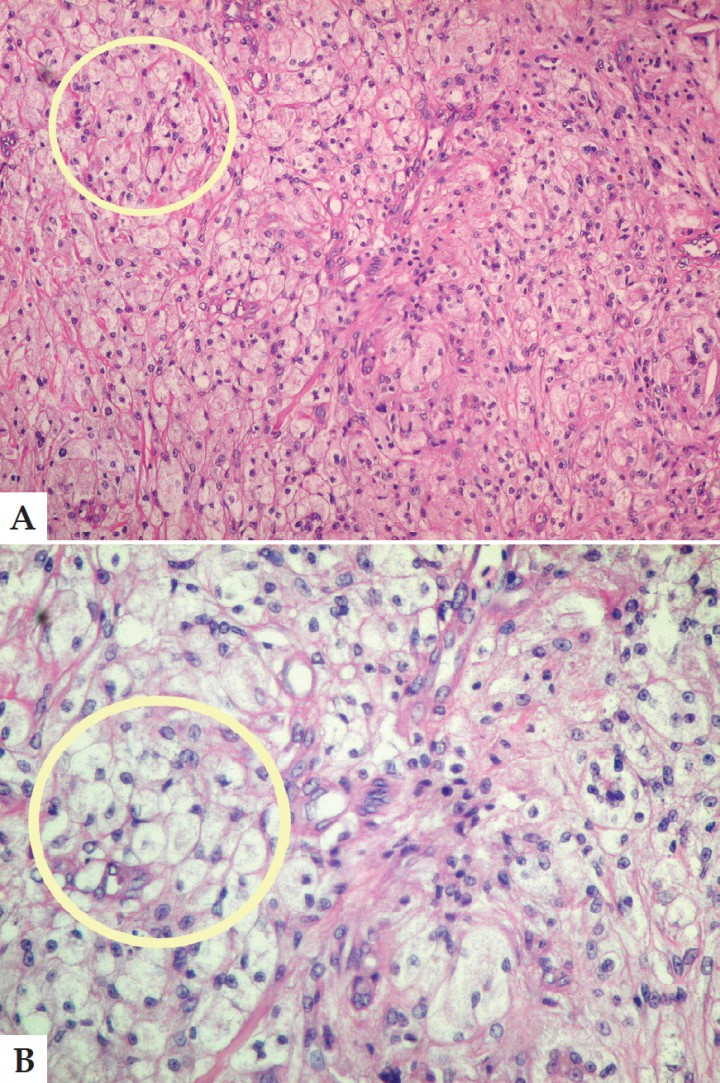

Inicialmente el caso se consideró como un adenoma de la glándula uropigial, pero posteriormente se realizaron pruebas inmunohistoquímicas y tinción con azul de toluidina comprobando la presencia de gránulos metacromáticos que, sumados a las características propias de las células, permitió concluir que estábamos ante un diagnóstico de mastocitoma, descartando el inicial de adenoma de glándula uropigial (Figs. 2 A y B).

<p>A. Corte histológico. Conjunto de células redondas características del proceso (círculo amarillo). Tinción Hematoxilina-Eosina Aumento 40x. B. Corte histológico. Tinción con azul de toluidina, donde es posible apreciar abundantes gránulos metacromáticos (flechas). Aumento 1000x.</p>

A. Corte histológico. Conjunto de células redondas características del proceso (círculo amarillo). Tinción Hematoxilina-Eosina Aumento 40x. B. Corte histológico. Tinción con azul de toluidina, donde es posible apreciar abundantes gránulos metacromáticos (flechas). Aumento 1000x.

Diagnóstico: Mastocitoma en la zona uropigial.